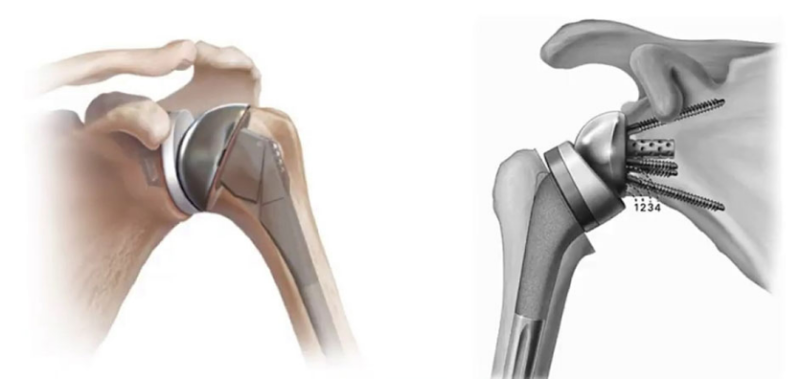

Il existe 2 types de prothèses selon l'origine et l'aspect de l'omarthrose

Prothèse anatomique

Elle est proposé devant une arthrose centré avec des tendons intacts

Prothèse inversée

Elle est indiqué pour les arthrose excentré avec des tendons rompus